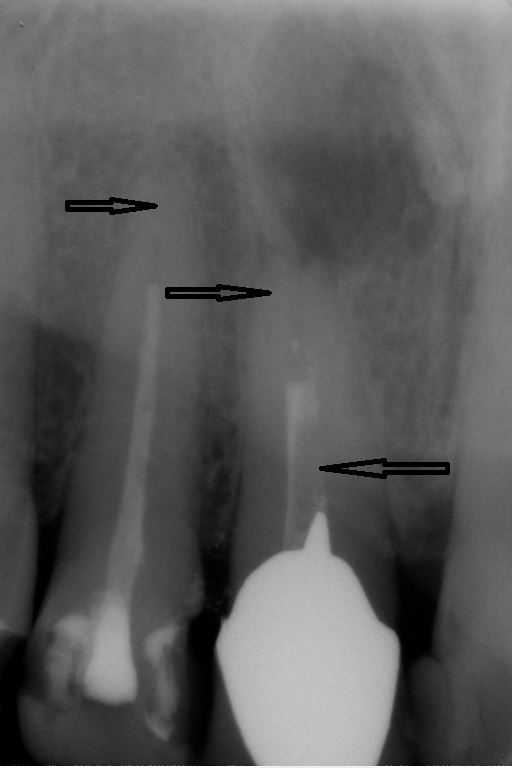

Fallbeispiel für eine große Entzündung an der Wurzel

Wurzel nach erfolgreicher Behandlung 2 Monate später schon fast ausgeheilt